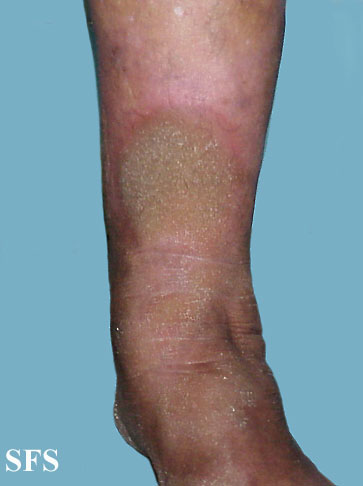

progressive palmoplantar keratoderma